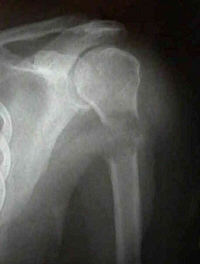

Refer to this picture for question 1.

1. Related features include: